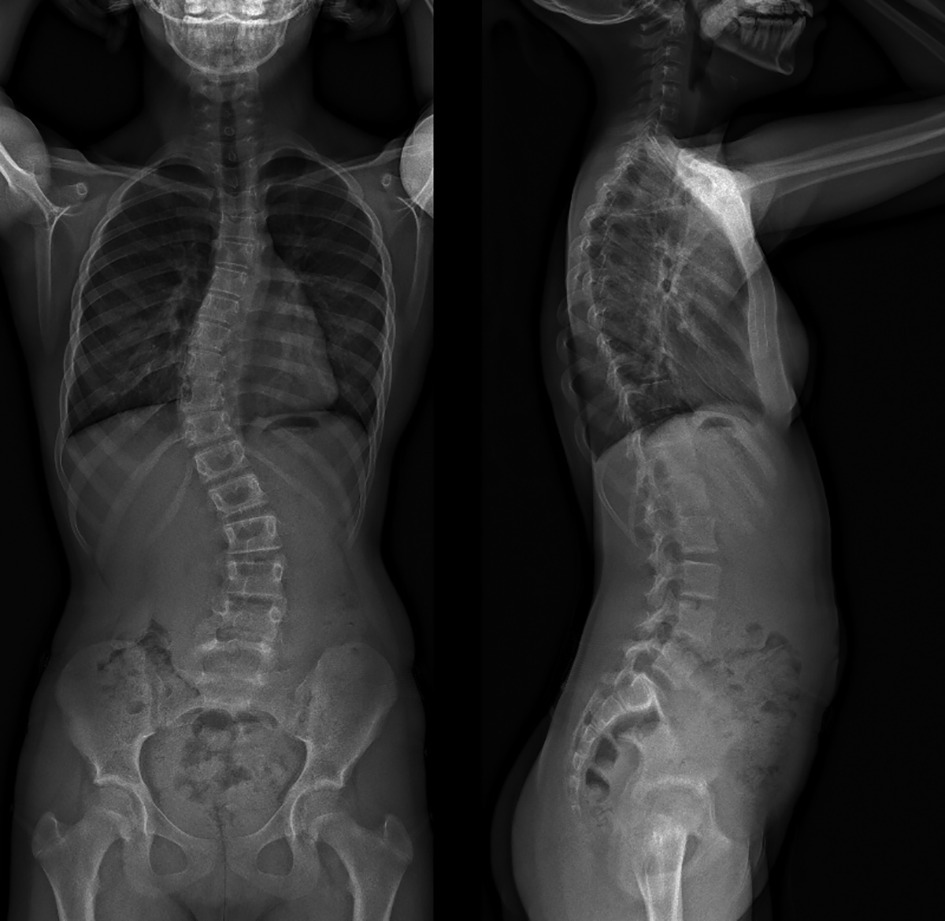

La découverte d’une gibbosité impose une radiographie du rachis en totalité debout de face et de profil (fig. 3). Il ne faut pas se contenter de clichés segmentaires.

Depuis quelques années, les techniques de stéréoradiographie (système EOS), moins irradiantes, fournissent des images de bonne qualité. Ces radios sont à privilégier lorsque le suivi de l’enfant ou de l’adolescent impose de répéter les clichés.